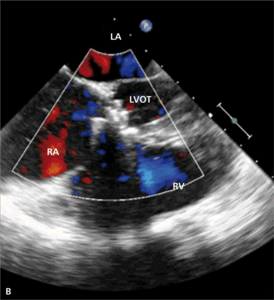

Rycina 4. Wynik przezskórnego leczenia defektu Gerbode w trójwymiarowej echokardiografii przezprzełykowej [A], w 64-rzędowej tomografii komputerowej [B].

W badaniu echokardiograficznym może dojść do omyłkowej interpretacji strumienia przecieku do prawego przedsionka jako fali zwrotnej przez zastawkę trójdzielną, a w konsekwencji do rozpoznania ciężkiego nadciśnienia płucnego [28]. Pomocą we właściwej interpretacji uzyskanego obrazu może być echokardiografia trójwymiarowa czasu rzeczywistego [29].

Leczenie zabiegowe nabytej wady typu Gerbode to przede wszystkim ponowny zabieg kardiochirurgiczny. Szacowana na podstawie danych sprzed kilkudziesięciu lat śmiertelność okołozabiegowa wynosi około 16% [25]. Gdy nie ma aktywnego zapalenia wsierdzia i przy współistnieniu korzystnych warunków anatomicznych możliwe jest również przezskórne zamknięcie ubytku. Zastosowanie znalazły tutaj zapinki do mięśniowego VSD [30], ubytku w przegrodzie międzyprzedsionkowej (atrial septal defect, ASD) [31] czy PDA [32]. W ośrodku autorów do zamknięcia tego typu ubytku u chorego po AVR (zastawka Sorin Pericarbon) użyto zatyczki dedykowanej do okołobłoniastego VSD (perimembranous VSC, pmVSD), uzyskując pełne zamknięcie ubytku (ryc. 3, 4). Podobnie jak w przypadku innych implantacji zatyczek w okolicę mechanicznej zastawki serca, podstawowym problemem jest taki dobór urządzenia, aby zminimalizować prawdopodobieństwo zablokowania dysków zastawki przy jednocześnie możliwie całkowitym wypełnieniu ubytku.